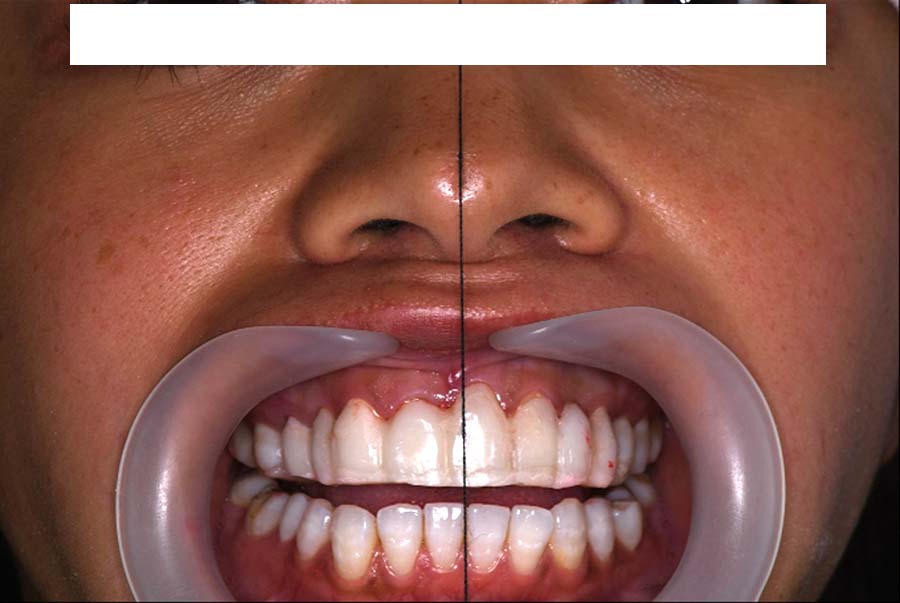

噛み合わせ治療の症例24

スプリント使用後、

補綴治療をした症例

| 治療内容 | ①スプリントを装着 ②副子を装着 ③2024年4月 口腔内反映開始 ④副子を入れた状態の所まで咬合を挙上 (バイトアップ) ⑤2024年5月 上顎前歯部8本に仮歯(TEK) を装着 |

初診日 2023年10月12日